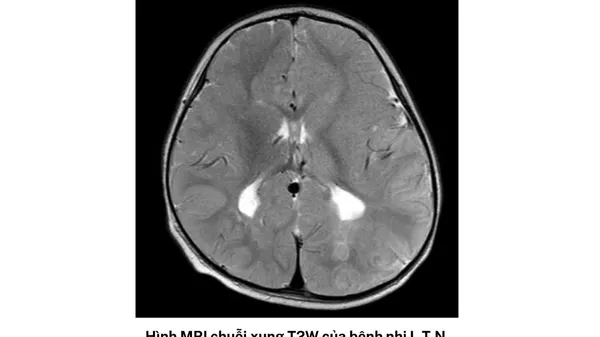

Trường hợp thứ hai là bệnh nhi nữ, sinh năm 2020, tại TPHCM nhập khoa vào ngày cuối tháng 5.

Bé có tiền sử động kinh toàn thể từ 14 tháng tuổi và đang điều trị Depakin. Qua 10 ngày tích cực điều trị, tri giác bé có cải thiện chậm, có nhịp tự thở tốt và cai được máy thở, tiếp tục kiểm soát động kinh và vật lý trị liệu vận động.

Hội chứng hai bé gặp phải còn gọi là hội chứng HHE, là một bệnh hiếm gặp được phát hiện lần đầu vào năm 1960. Bệnh có trạng thái co giật nửa người kéo dài trên trẻ sốt dưới 4 tuổi, gây liệt nửa người cùng bên co giật và teo não bán cầu đối bên.

Bác sĩ Việt nhấn mạnh, ở giai đoạn cấp tính, bệnh nhân xuất hiện nhiều cơn co giật khó kiểm soát, tổn thương và phù não một bên bán cầu não. Nếu không kiểm soát tốt, bệnh nhân có thể liệt nửa người suốt đời, di chứng não và sống đời sống thực vật, thậm chí có thể tụt não dẫn đến tử vong.